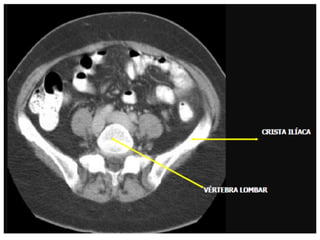

• O volume é definido pelo diafragma até a

extremidade superior da crista ilíaca.

Varredura da Pelve

• Os limites são definidos pela extremidade

superior da crista ilíaca até a extremidade

Imagem de corte axial com

janela para tecido ósseo